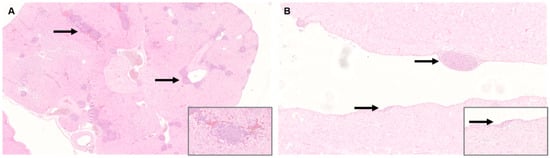

In the digestive system, most striking lesions were non-purulent ganglionitis, neuritis, and lymphoid hyperplasia in crop, proventriculus, gizzard, and intestine. Changes were more severe in the juvenile cockatiels than in the adults, particularly in the proventriculus (Figure 2A,B) and intestines (Figure 2C,D). Overall, 1/11 juvenile cockatiel developed severe lesions in the crop, 2/11 in the proventriculus, and 3/11 in the intestine, respectively. Furthermore, severe changes were found in the intestine of 1/11 adult cockatiel. One adult and one juvenile bird each did not reveal any histologic changes in the aforementioned organs.

Figure 2. Histology of gastrointestinal tissue of Parrot bornavirus 4 (PaBV-4)-infected adult and juvenile cockatiels. (A) Proventriculus of adult cockatiel A 0,1. Mild non-purulent ganglionitis (arrow); original magnification x100, magnification of insert ×400. (B) Proventriculus of juvenile cockatiel J 2. Severe non-purulent ganglionitis (arrow), neuritis, and lymphoid hyperplasia; original magnification ×100, magnification of insert ×400. (C) Intestine of adult cockatiel E 1,0. Moderate ganglionitis, neuritis, and lymphoid hyperplasia (arrow) and mononuclear infiltration of the lamina propria; original magnification ×100. (D) Intestine of juvenile cockatiel J 6. Severe non-purulent ganglionitis, neuritis, and lymphoid hyperplasia (arrow) and mononuclear infiltration of the lamina propria; original magnification ×100; hematoxylin and eosin staining (H&E).